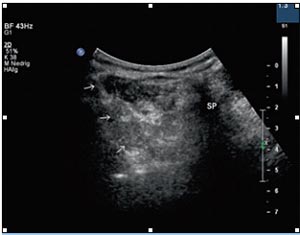

تصاویر سونوگرافی حین انجام بلاک:

با استفاده از تصویربرداری سونوگرافی محل عصب مشخص می شود. در نهایت سوزن وارد کمر می شود و تحت گاید سونوگرافی به سمت محل عصب هدایت می شود و تزریق انجام می شود.